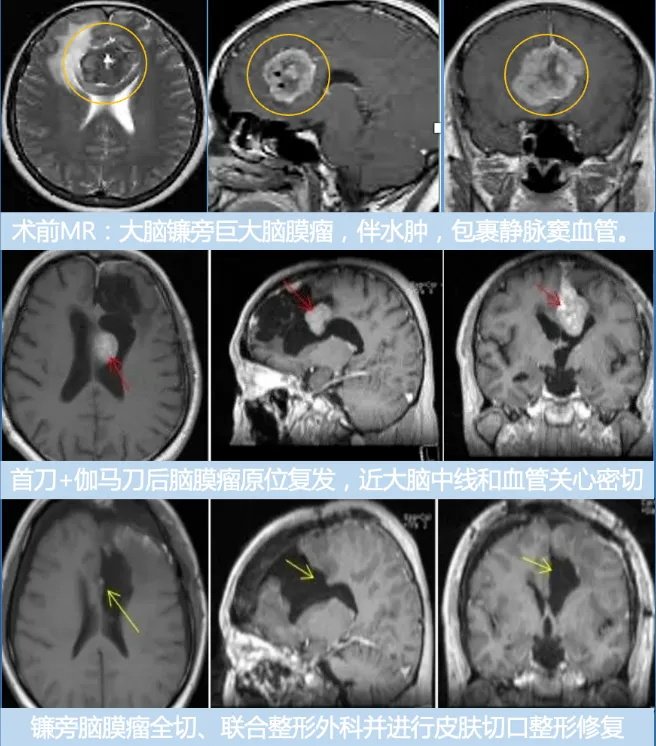

病情回顾:四十多岁赵先生因突发癫痫就医,家人带其MRI检查后发现大脑左额镰旁脑膜瘤,立即在国内某知名医院进行部分切除。术后需要反复伽马刀治疗,没想到3年后脑膜瘤恶化复发为多发脑膜瘤,复查核磁显示大脑镰前段基本均受累,并有大脑镰右侧肿瘤生长,矢状窦被累及,左侧额部凸面硬脑膜多处肿瘤生长。

在术中iMRI、术中神经导航等设备的辅助下,巴特朗菲教授为赵先生实施了手术,大脑镰旁及矢状窦旁的肿瘤被完全切除,并保护了正常的脑组织结构。赵先生术后第二天下床进行康复锻炼。神经功能无任何异常,术后13天步行出院。

▼赵先生术前术后MR对比